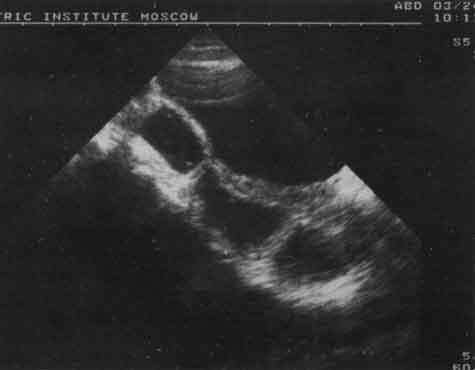

90% обследованных детей с хроническими запорами имели функциональные отклонения толстой кишки в виде гипотонии и гипертонии стенок. Для гипотонуса были характерны легкая податливость стенок кишки при введении жидкости, расширение ампулы прямой кишки, сигмовидной кишки, отсутствие сопротивления току жидкости со стороны ректосигмоидного сфинктера и нечеткое разделение им просвета кишок. При гипертонусе все эти признаки были противоположны - незначительное расширение обеих кишок, четкая визуализация ректосигмоидного сфинктера и наличие дополнительных сфинктеров в просвете сигмовидной кишки, ее выраженная гаустрация. У ряда детей имело место сочетание гипо- и гипертонуса сигмовидной и прямой кишки. Эти два состояния имеют довольно четкую связь с возрастом для новорожденных, грудных детей и детей раннего возраста: более характерен гипертонус дистальных отделов толстой кишки.

Видимая на эхограммах стенка кишки, особенно прямой, состоит из трех слоев: наружного гиперэхогенного - серозного, среднего гипоэхогенного - мышечного и внутреннего эхогенного - слизистой. Наибольшие изменения при хроническом запоре претерпевает мышечный слой. В норме его толщина вне зависимости от возраста не превышает 2 мм. При длительном запоре толщина этого слоя может увеличиваться до 10 мм, нарушается его равномерность, т.е. развивается гипертрофия. При развитии процесса в гипоэхогенном мышечном слое появляются участки уплотнения в виде линейных тонких эхосигналов, происхождение которых связано с развитием участков склероза. Если гипертрофические изменения в мышечном слое носят, как правило, обратимый характер, то визуализация участков склероза в стенке кишки может быть расценена как патологический процесс. Перечисленные вторичные изменения в стенках толстой кишки характерны как для гипотонуса, так и для гипертонуса (рис. 7, 8).

Рис. 7. Эхограмма прямой и сигмовидной кишки (продольный срез) при гипотонусе.

Рис. 8. Эхограмма прямой и сигмовидной кишки (продольный срез) при гипертонусе.